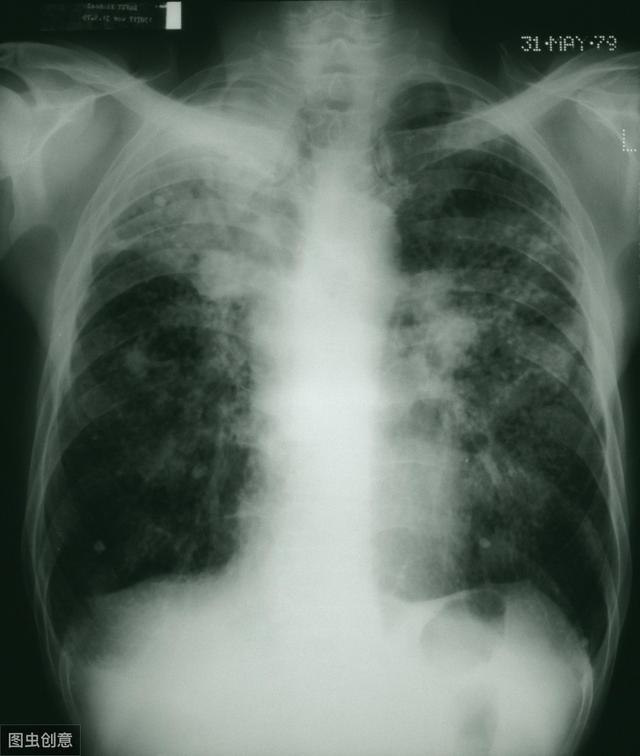

粉塵の多い環境での労働は呼吸器や肺に大きな影響を及ぼし、人体に最も深刻な影響を及ぼすのは「じん肺症」である。じん肺症とは、簡単に言えば、肺に沈着した粉塵が肺組織のびまん性線維化を引き起こし、結節や瘢痕を形成することであり、最も深刻なのは呼吸不全や誘発性肺がんに至ることである。

じん肺は患者の生命に深刻な影響を与える。 肺組織の線維化により、患者は呼吸困難の進行性悪化に苦しみ、最終的には呼吸不全に陥る。恐ろしいのは、肺組織の線維化に対する特効薬がないことで、これがこの病気の最も恐ろしい点である。